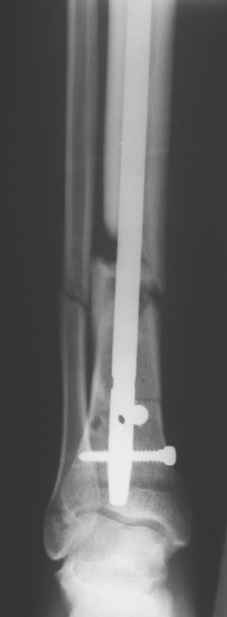

Сегодня прооперировали без открывания. Хотел-бы услышать комментарии по поводу послеоперационной нагрузки.

Учитывая изначальные снимки и то. что сделали , не открывая - весьма достойно. Доктор Коган прав - перелом немного перерастянут ( что хорошо видно по фибуле), а перерастянутые переломы большеберцовой срастаются очень плохо. Поэтому я бы обязательно дал раннюю динамизацию - на 6 неделях ( когда можно не опасаться малротации) разблокировал бы проксимальный фрагмент полностью и начал бы нагружать ногу. Будьте готовы к остеотомии ( или остеоэктомии участка) малоберцовой чеерз несколько месяцев- уж слишком хорошо стоит - очень вероятно, что срастется рано и будет держать большеберцовую перерастянутой

вдогонку - до разблокирования нагружать противопоказано - все, чего добьетесь - погнете шурупы. причем, если погнете дистальные ( как обычно бывает) - гвоздь провалится в сустав. Нагружайте птолько после проксимальной динамизации, когда будете уверены, что гвоздь поднагрузкой будет смещаться вверх, а не вниз